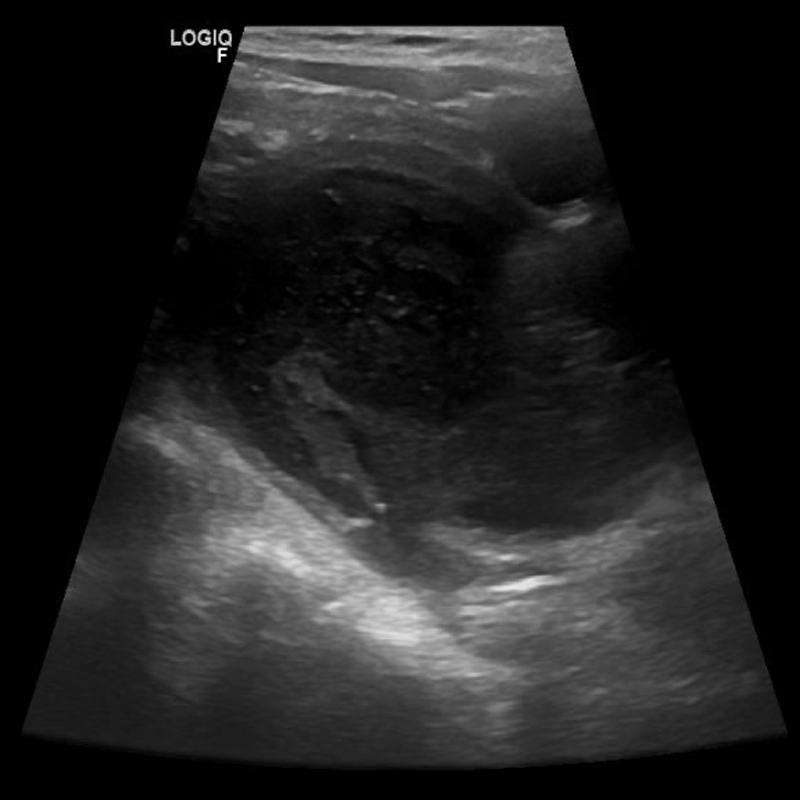

Octubre 2020. Instituto Modelo de Cardiología Presentado por: Instituto Modelo de Cardiología Disuria, 2 años y 10 meses.